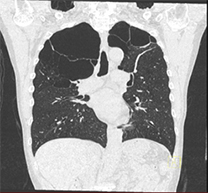

慢性閉塞性肺疾患

肺がん、慢性閉塞性肺疾患(COPD)など。